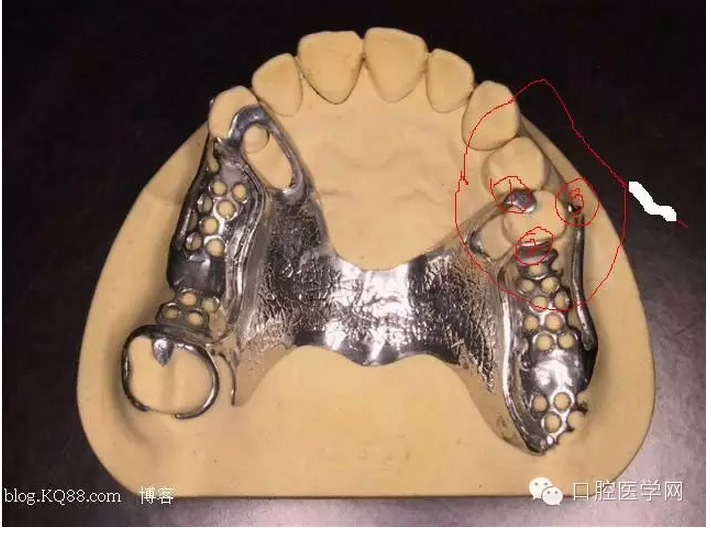

先注明一下:本文圖片部分來自李望松的支架設(shè)計(jì)圖譜收集u/210/archives/2008/25181.html,借圖表達(dá)一下,沒有別的目的,只是讓文章更生動些,李老師一直是我崇拜的偶像,只是近來很少見到他的文章,期待李老師的大作,言歸正傳——————修復(fù)大夫要精通支架設(shè)計(jì),作為一個修復(fù)大夫,是第一個獲得患者牙體狀況的,所以說在哪放個合支拖,在哪放個卡換,至關(guān)重要,因?yàn)槲覀冏龅氖莻€有創(chuàng)不可逆操作,既要兼顧牙周狀況,又要兼顧粘膜狀況,以及牙槽脊的情況,所以說當(dāng)給患者做完檢查以后我們頭腦中就應(yīng)該有一個大體支架了,以前,總是太依賴加工廠了,取完模剩下的好像都是交給了加工廠了,怎么設(shè)計(jì),你看摸著辦吧,仿佛設(shè)計(jì)那是加工廠的事,可是做了幾回再加上自己的學(xué)習(xí),經(jīng)驗(yàn),加工廠的設(shè)計(jì)總是不怎么樣,以前設(shè)計(jì)的方案仿佛根深蒂固,一直就認(rèn)為那是正確的就那么設(shè)計(jì),再加上以前看過支抗兄的一篇文章,也是深有感觸,一個不科學(xué)的設(shè)計(jì)方案,那樣就成了一個慢性拔牙器。看看幾幅圖片

看紅箭頭處為什么要空出一點(diǎn)距離?,看看自己加工廠設(shè)計(jì)的不管牙怎樣是不是都成了一個整體呢?對于愕板或者是

愕桿要離開齦緣4-6mm,以促進(jìn)食物對牙齦的按摩沖刷作用,促進(jìn)牙齦健康

前愕桿要離開至少6mm如下圖